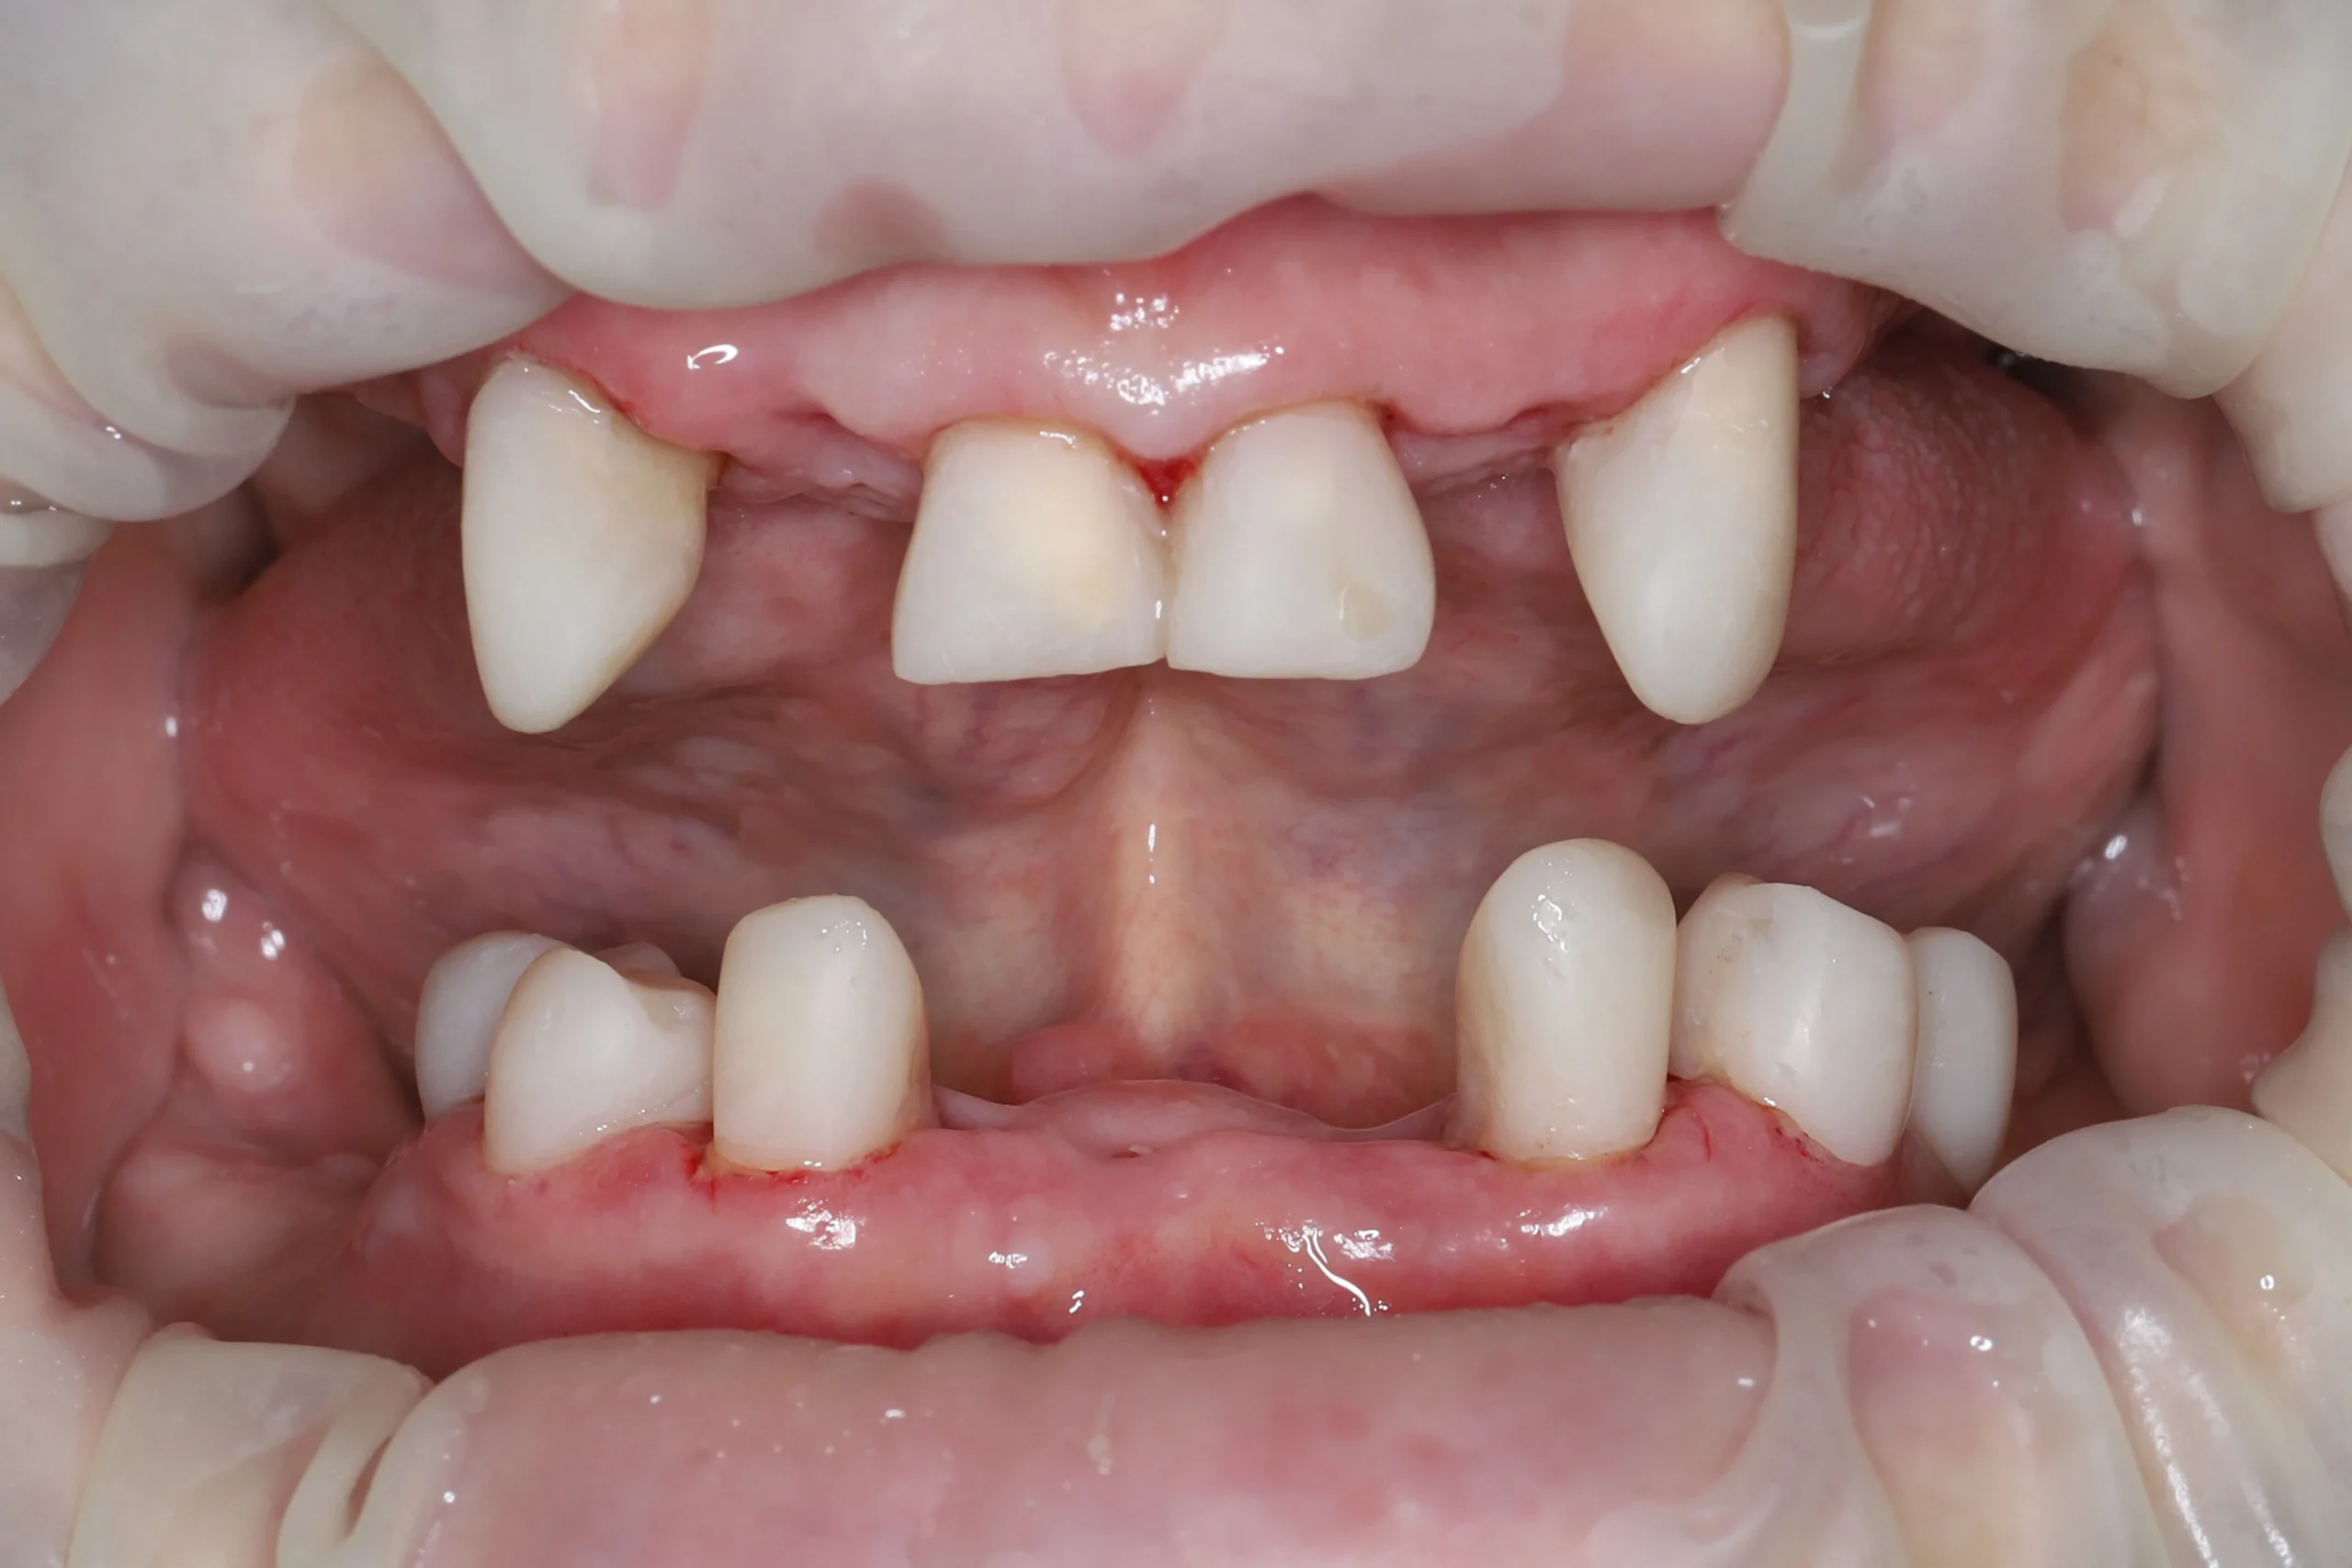

Выполнили эндодонтическое лечение зубов, сохраняемых для дальнейшего протезирования и восстановления функции. Корневые каналы обработали, запломбировали, пролечили кариес и восстановили анатомическую форму зубов. Сняли силиконовые оттиски под временные клинические коронки.

Ортопедическая подготовка

Поскольку у пациентки было значительное разрушение твёрдых тканей зубов и большие старые пломбы, в корневые каналы эндодонтически пролеченных зубов установили стекловолоконные штифты и сформировали культи под будущие коронки.

Сразу сняли цифровые оттиски внутриротовым сканером под PMMA-коронки и изготовили временные клинические коронки с помощью ранее полученных силиконовых оттисков.

Фиксация PMMA

На основе цифровых оттисков в лаборатории изготовили PMMA-коронки (промежуточные между временными клиническими и постоянными). Они обеспечили стабилизацию прикуса, восстановление и адаптацию слизистой полости рта перед имплантацией.